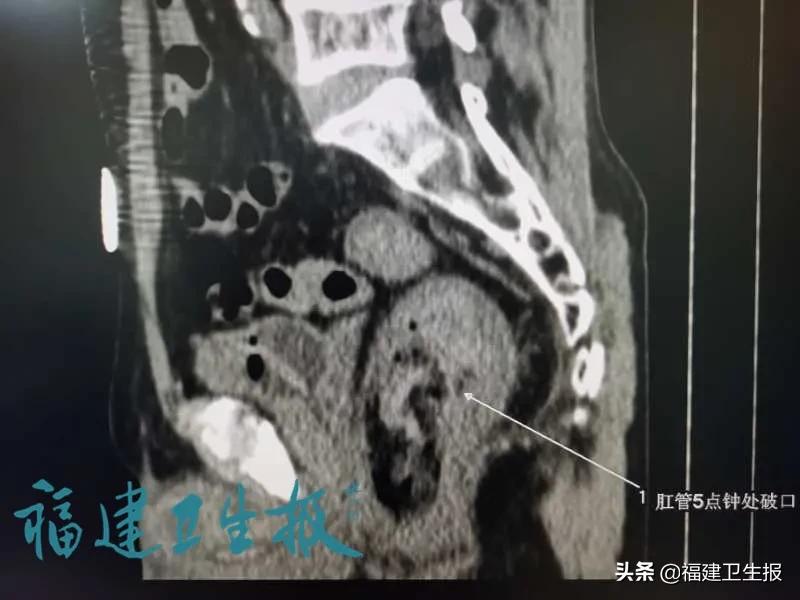

紧急安排CT检查,排除患者乙状结直肠肠穿孔,吴文宗团队诊断,张大爷用筷子导致直肠肛管损伤,引发直肠上静脉丛破裂出血,同时伴有失血性休克。